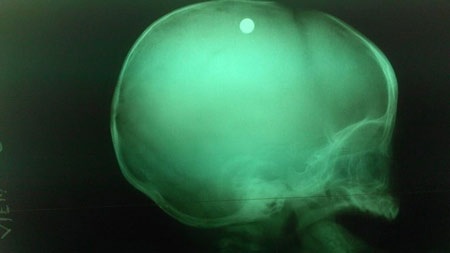

Các bác sĩ đã nhanh chóng xác định đây là trường hợp bị thương ở sọ não do hỏa khí gây ra, và cần phẫu thuật gấp vì kết quả chụp X - quang cho thấy viên đạn vẫn còn nằm trong sọ của bé.

Theo bác sĩ Đặng Xuân Vinh, viên đạn nằm trong nhu mô não, cách xương sọ 2cm.

“Đạn được bắn thẳng vào não. Đường đi của viên đạn này từ chẩm trái xuyên qua xương sọ vào nhu mô não, rồi lên đỉnh trái, cuối cùng chuyển hướng sang đỉnh phải đầu. Vì thế nhu mô não của bệnh nhi này bị tàn phá nặng, kèm xuất huyết não”, bác sĩ Vinh cho hay.